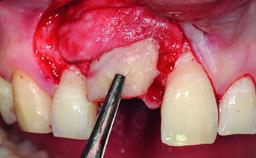

| Bone Augmentation | Horizontal|Simultaneous|Staged |

| Augmentation Materials | Autogenous chips|Xenogenous|Membrane |